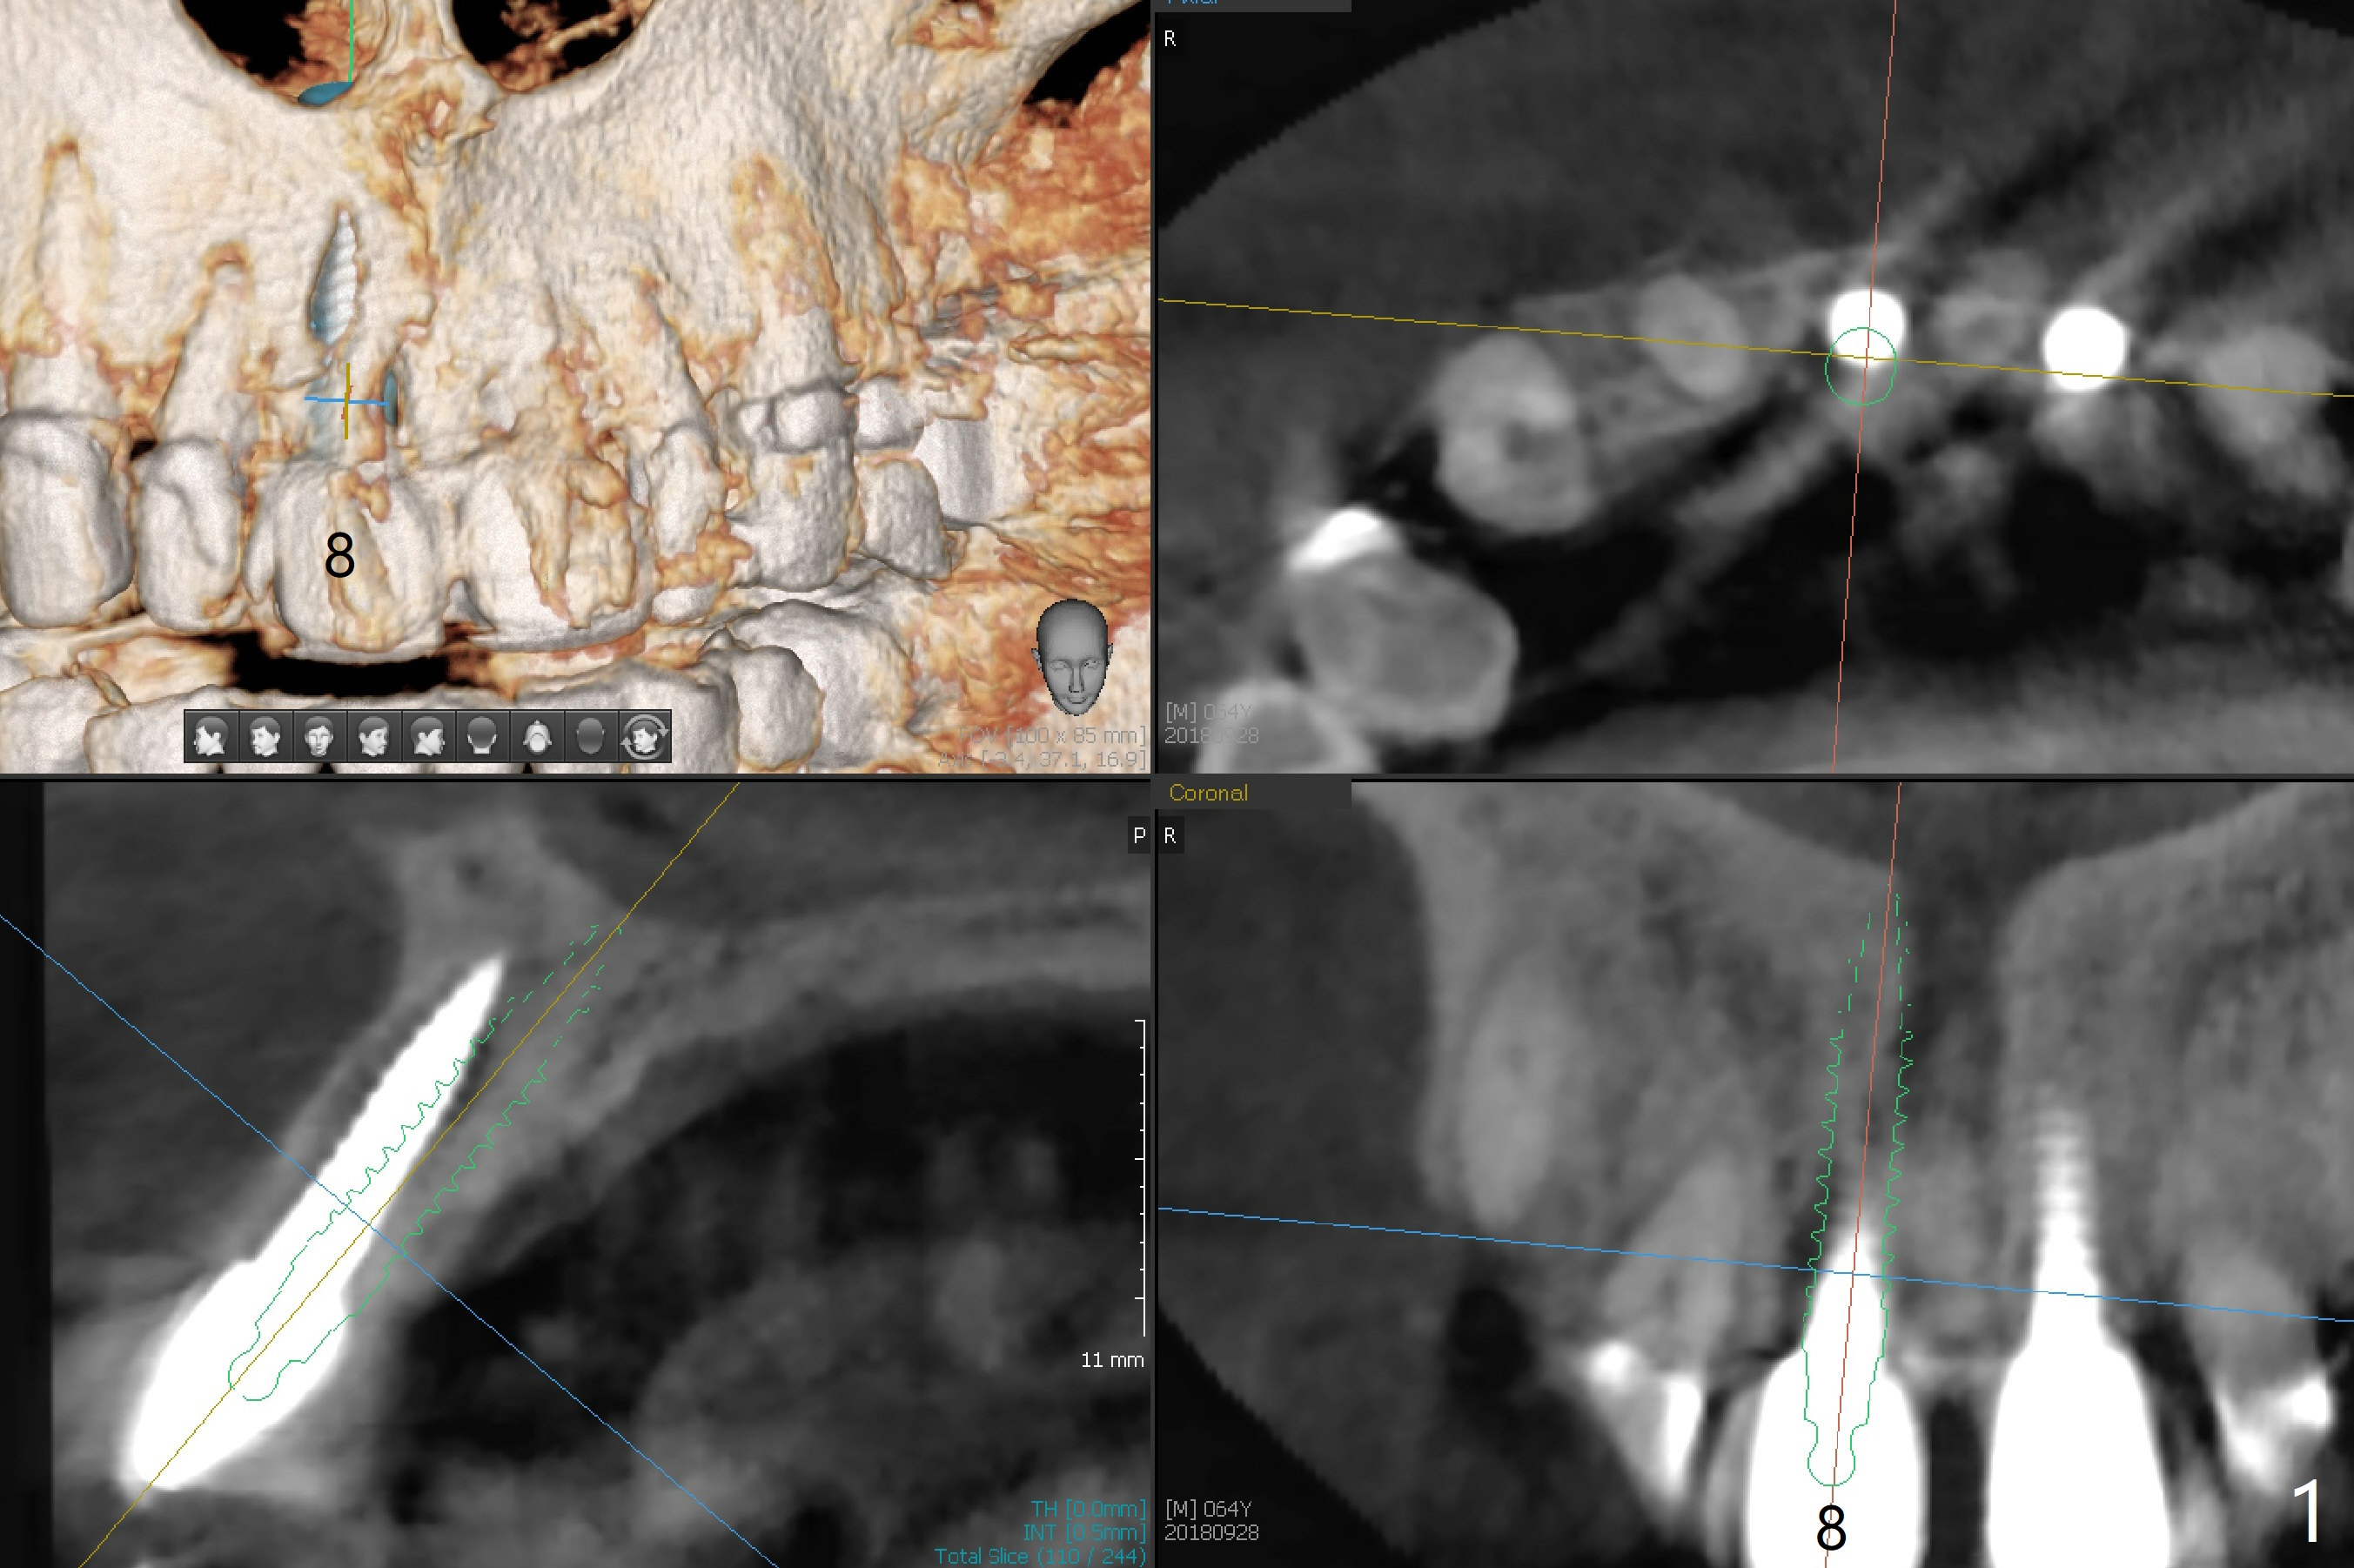

Reanalysis of preop CBCT shows a longer implant (3x16mm, green) to be placed palatal should be able to solve buccal plate bone loss associated with the previous 3x14 mm one at #8 (Fig.1). After crown/implant removal (with ease), a new palatal osteotomy is initiated flapless with 1.2 mm drill for 16 mm (palatal gingival margin, Fig.2). Following 1.5 mm drill for ~ 17 mm, a 3x16(2) mm 1-piece implant is placed >40 Ncm (Fig.3). After bone graft through limited access and abutment preparation, an immediate provisional is fabricated with clearance. The provisional dislodges repeatedly, mainly due to palatal perforation. It gets lost while the patient travels to his home country. Although there seems to be bone loss around the implant 2.5 months postop (Fig.4), the gingiva looks healthy. A new provisional is fabricated without impression. Because of short vertical height and small abutment diameter as well as bruxism, the provisional easily dislodges. The patient will return for impression 4 months 10 days postop. The bone loss remains 4 months postop when impression is taken (Fig.5).